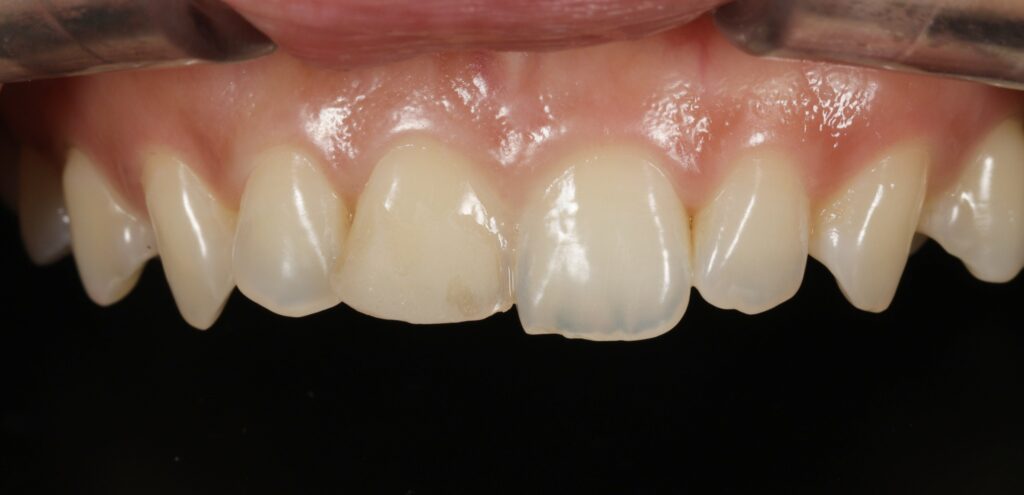

구강 내 모습을 확인해 보면

상악 중절치의 절단 부위가

약 1/3 정도 파절된 것을

관찰할 수 있는데요.

다행히 치수가 노출되지 않은

법랑질-상아질 파절로 확인됩니다.